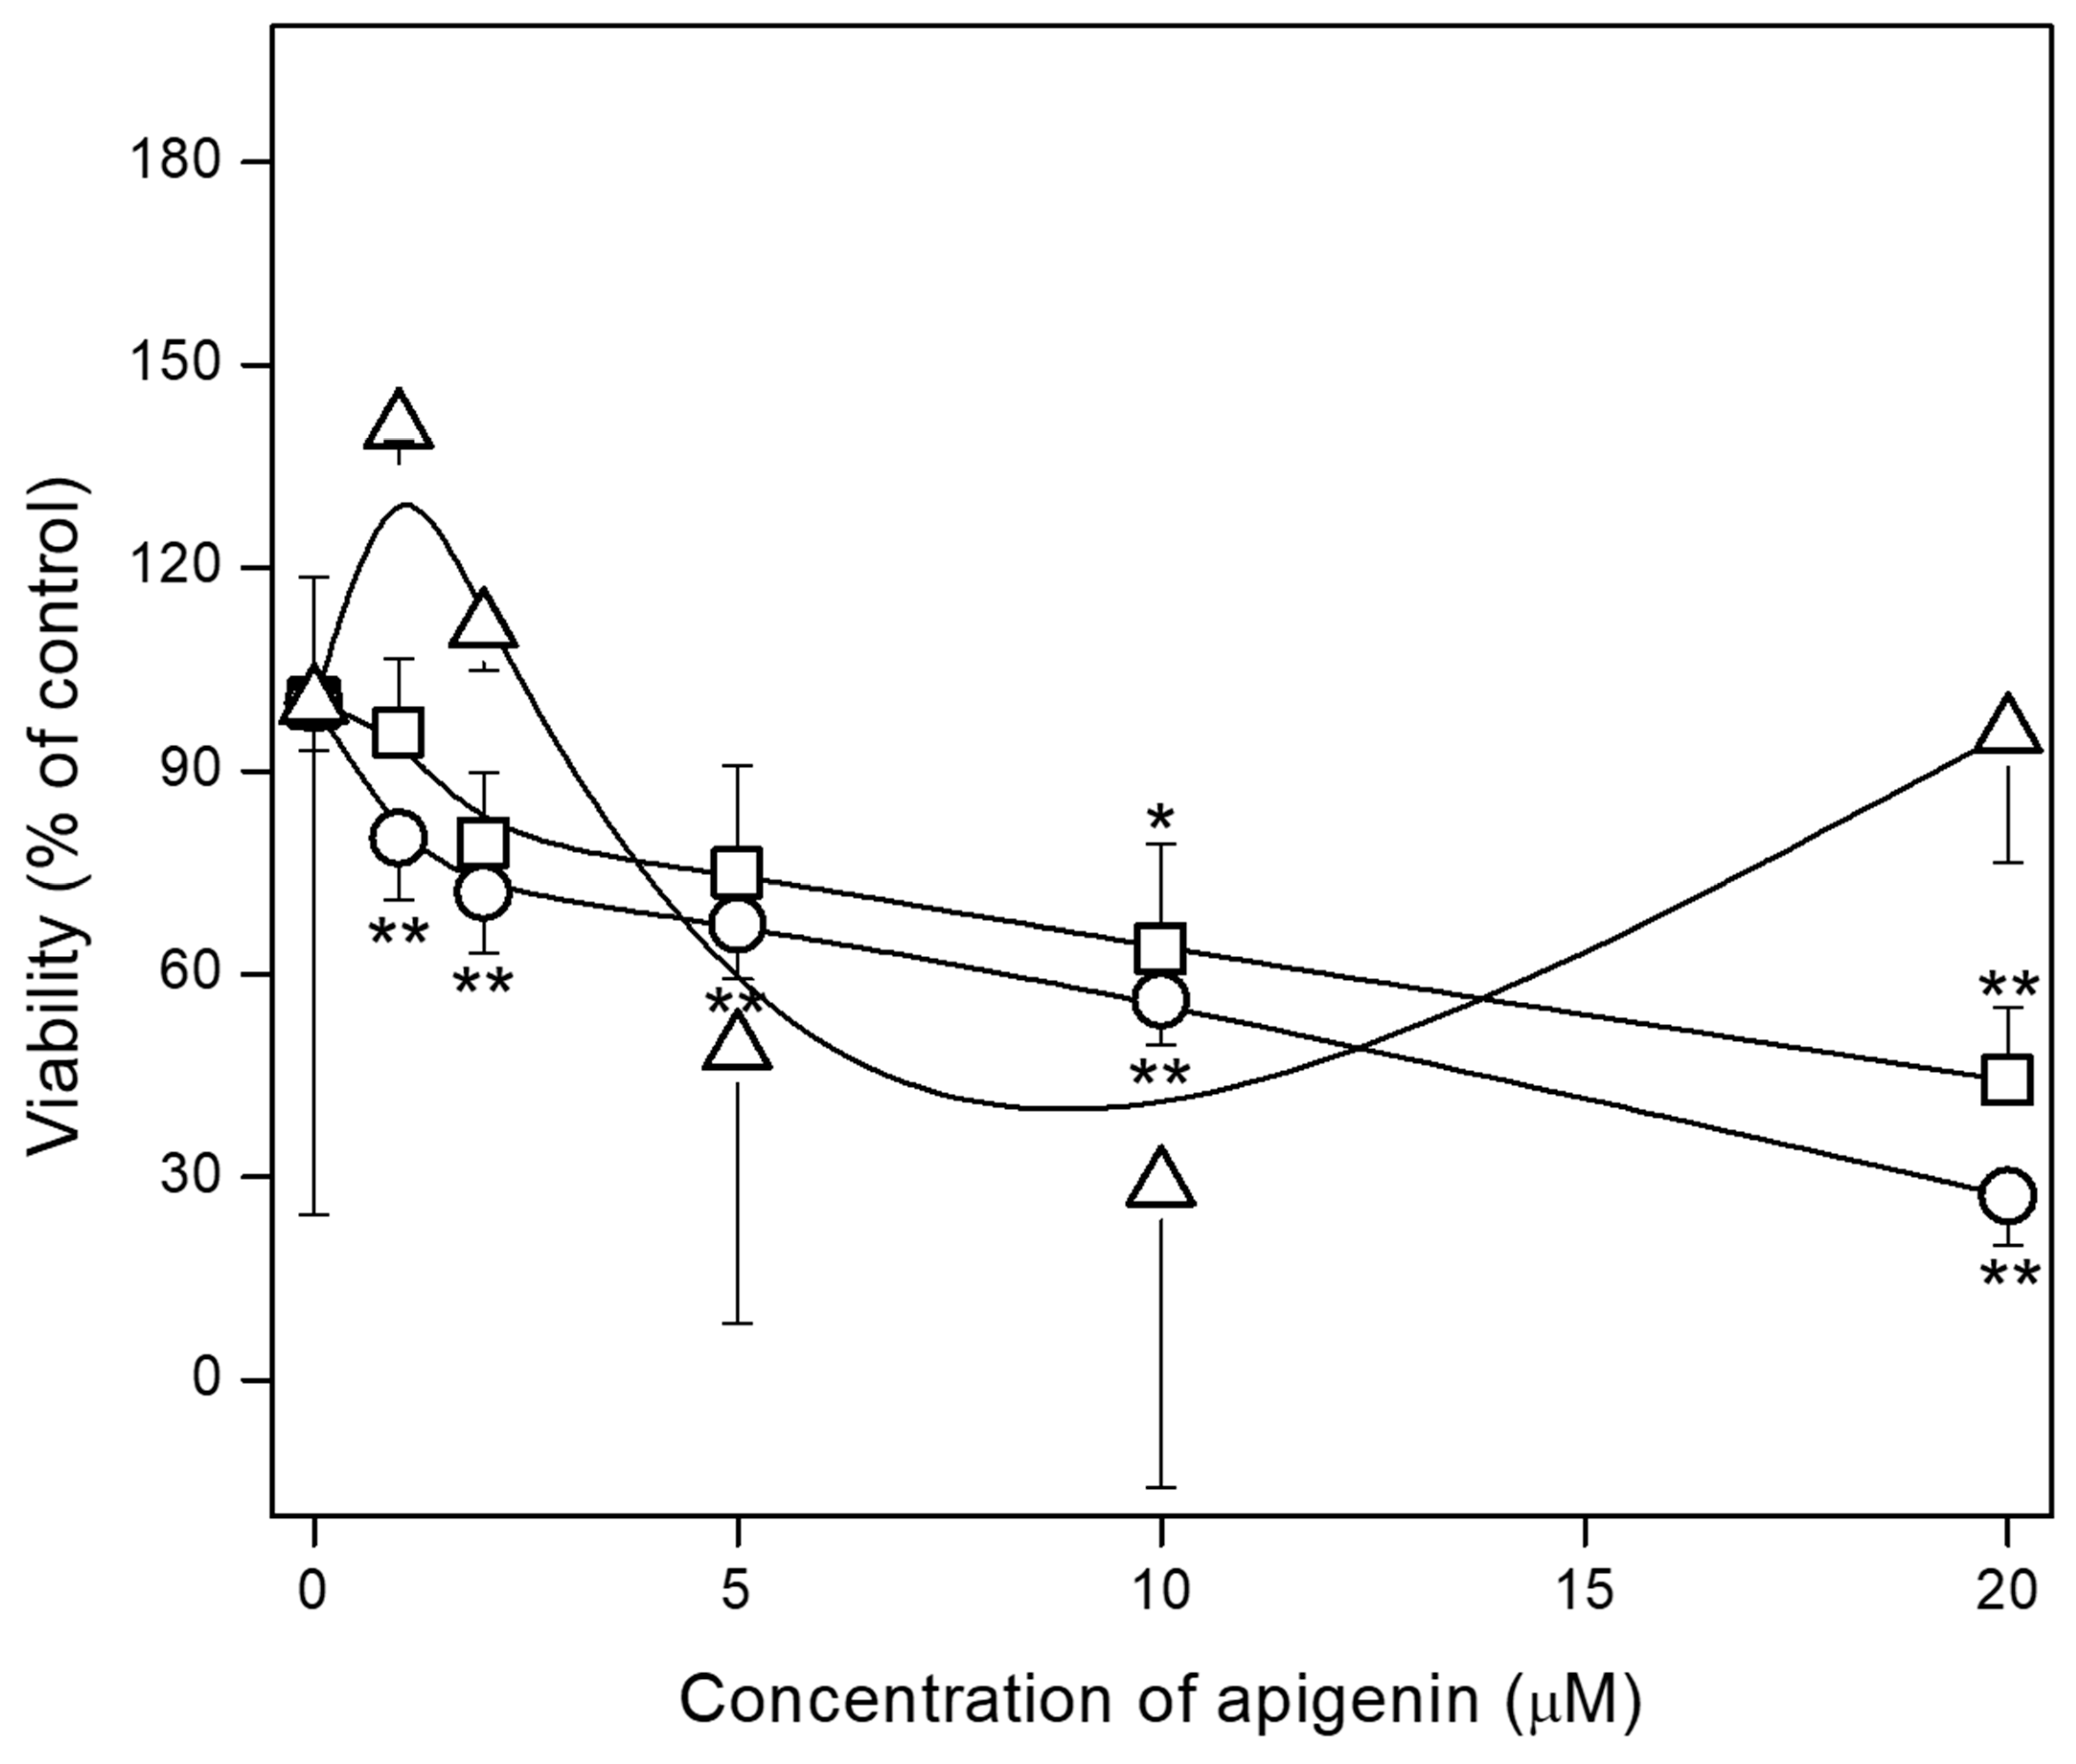

2.2. Effect of Apigenin on hFOB 1.19, Saos-2 and HCASMC Cell Proliferation

4.3. MTT Assay